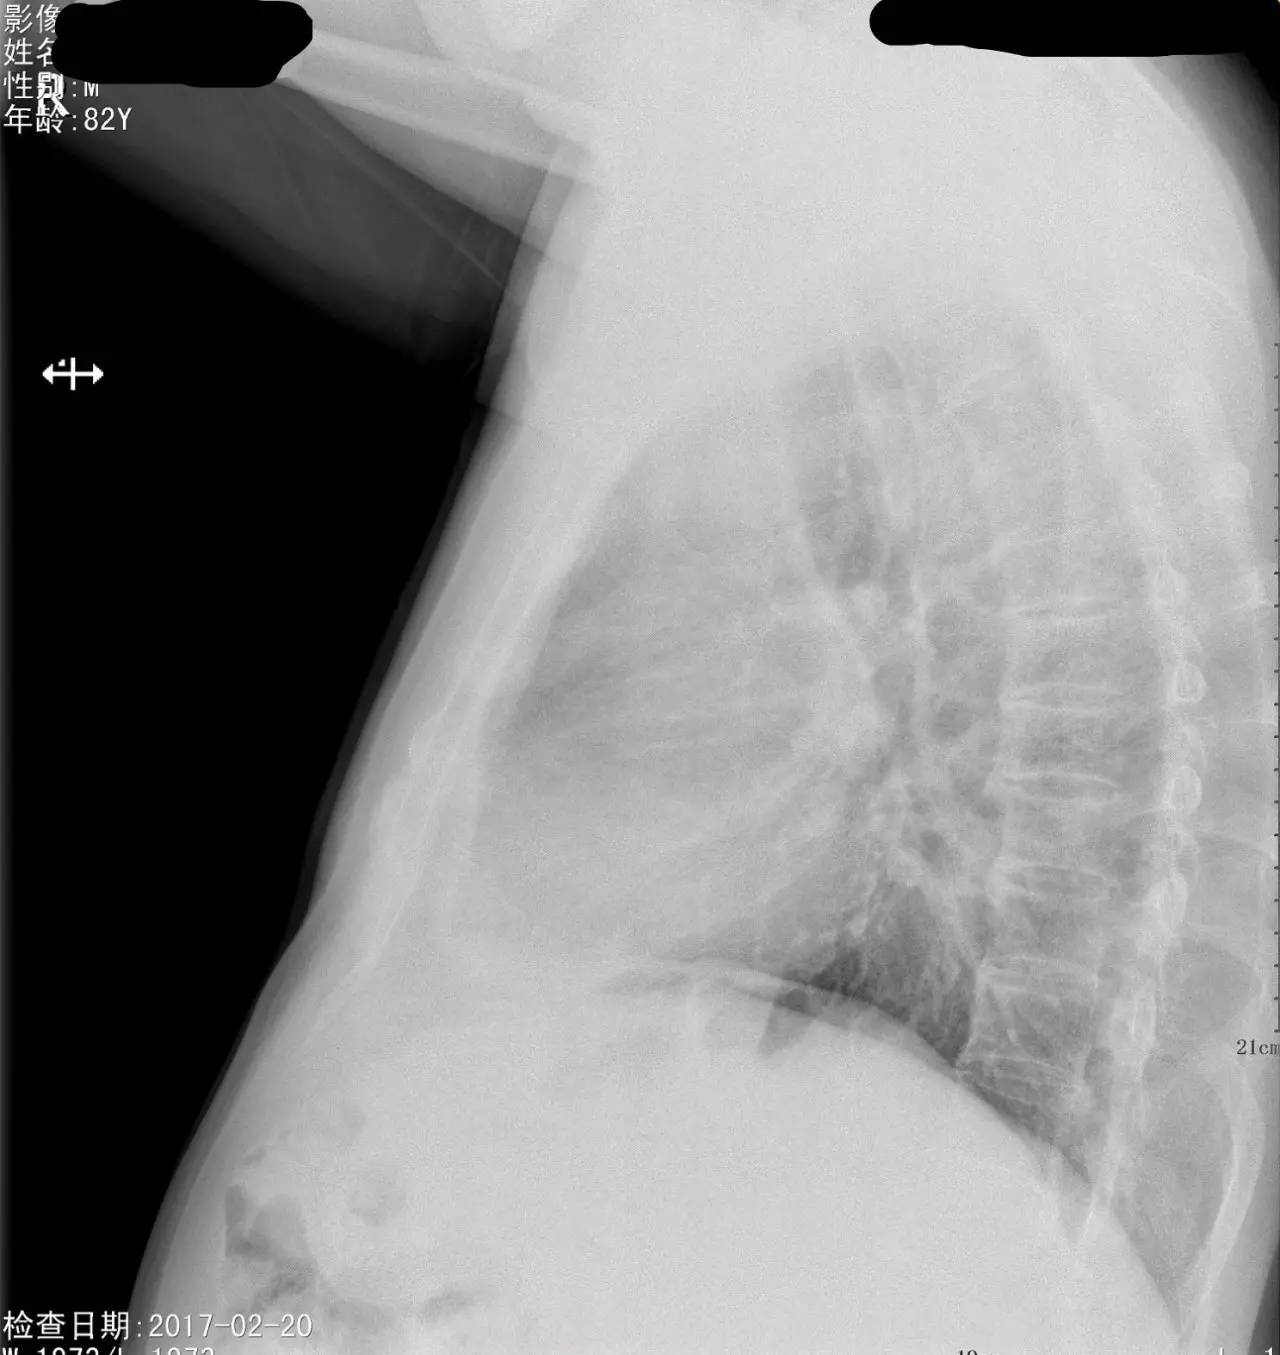

>>>>病例1:男 82岁 体检,患者自述无任何不适。

左下肺最有可能的诊断是?

A.包裹性积液

B.胸膜增厚

C.胸腔积液

D.心包脂肪垫